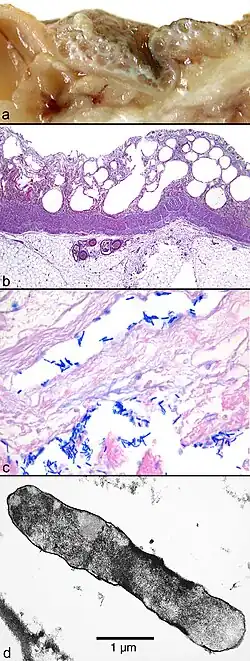

Macroscopic and microscopic findings from a patient who died from intestinal (bowel) gas gangrene

(a) Macroscopic picture of the edematous intestinal wall with multiple submucosal and subserosal cysts

(b) Histological picture of the intestinal mucosa with nonreactive necrosis

(c) Gram stain of cysts with large, rod-shaped bacteria

(d) Electron microscopic picture of a bacterium found in a submucosal cyst